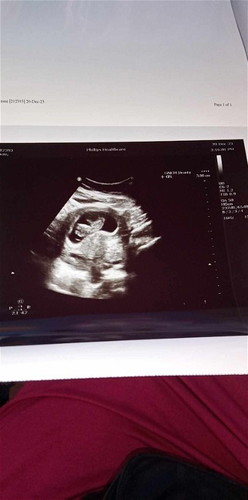

10w4dเห็นน้องแล้วค่ะ

ภาวนาทุกวันเครียดทุกวันหลังจากที่เคยแท้งเพราะท้องลมมาก่อนมาท้องนี้วิตกกังวลมาตลอดกลัวว่าจะท้องนี้จะท้องลมอีกวันนี้ไปซาวมาแล้วค่ะเจอน้องพร้อมหัวใจรู้สึกมีแรงมากขึ้นมีกำลังใจมากขึ้นค่ะ

ดีใจด้วยค่าคุณแม่ เห็นน้องเป็นตัวน้อยๆชัดมากเลย